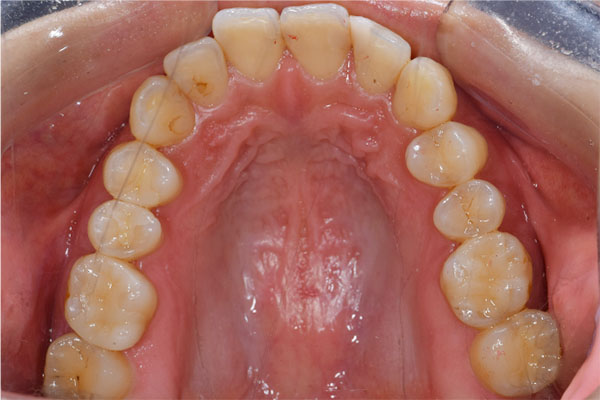

また左下の親知らずは虫歯のため抜歯、左下7番と5番はセラミックインレー、6番はFCZにて補綴しました。

※FCZ:ジルコニアより少しマイルドな硬さで審美性と機能面に優れているクラウン

全体の治療終了より1年半経過していますが、右下インプラント周囲に骨吸収の像など無く問題なく経過しています。またその他虫歯治療部位や歯の神経治療部位に関しても病変の所見は無く概ね良好と思われます。